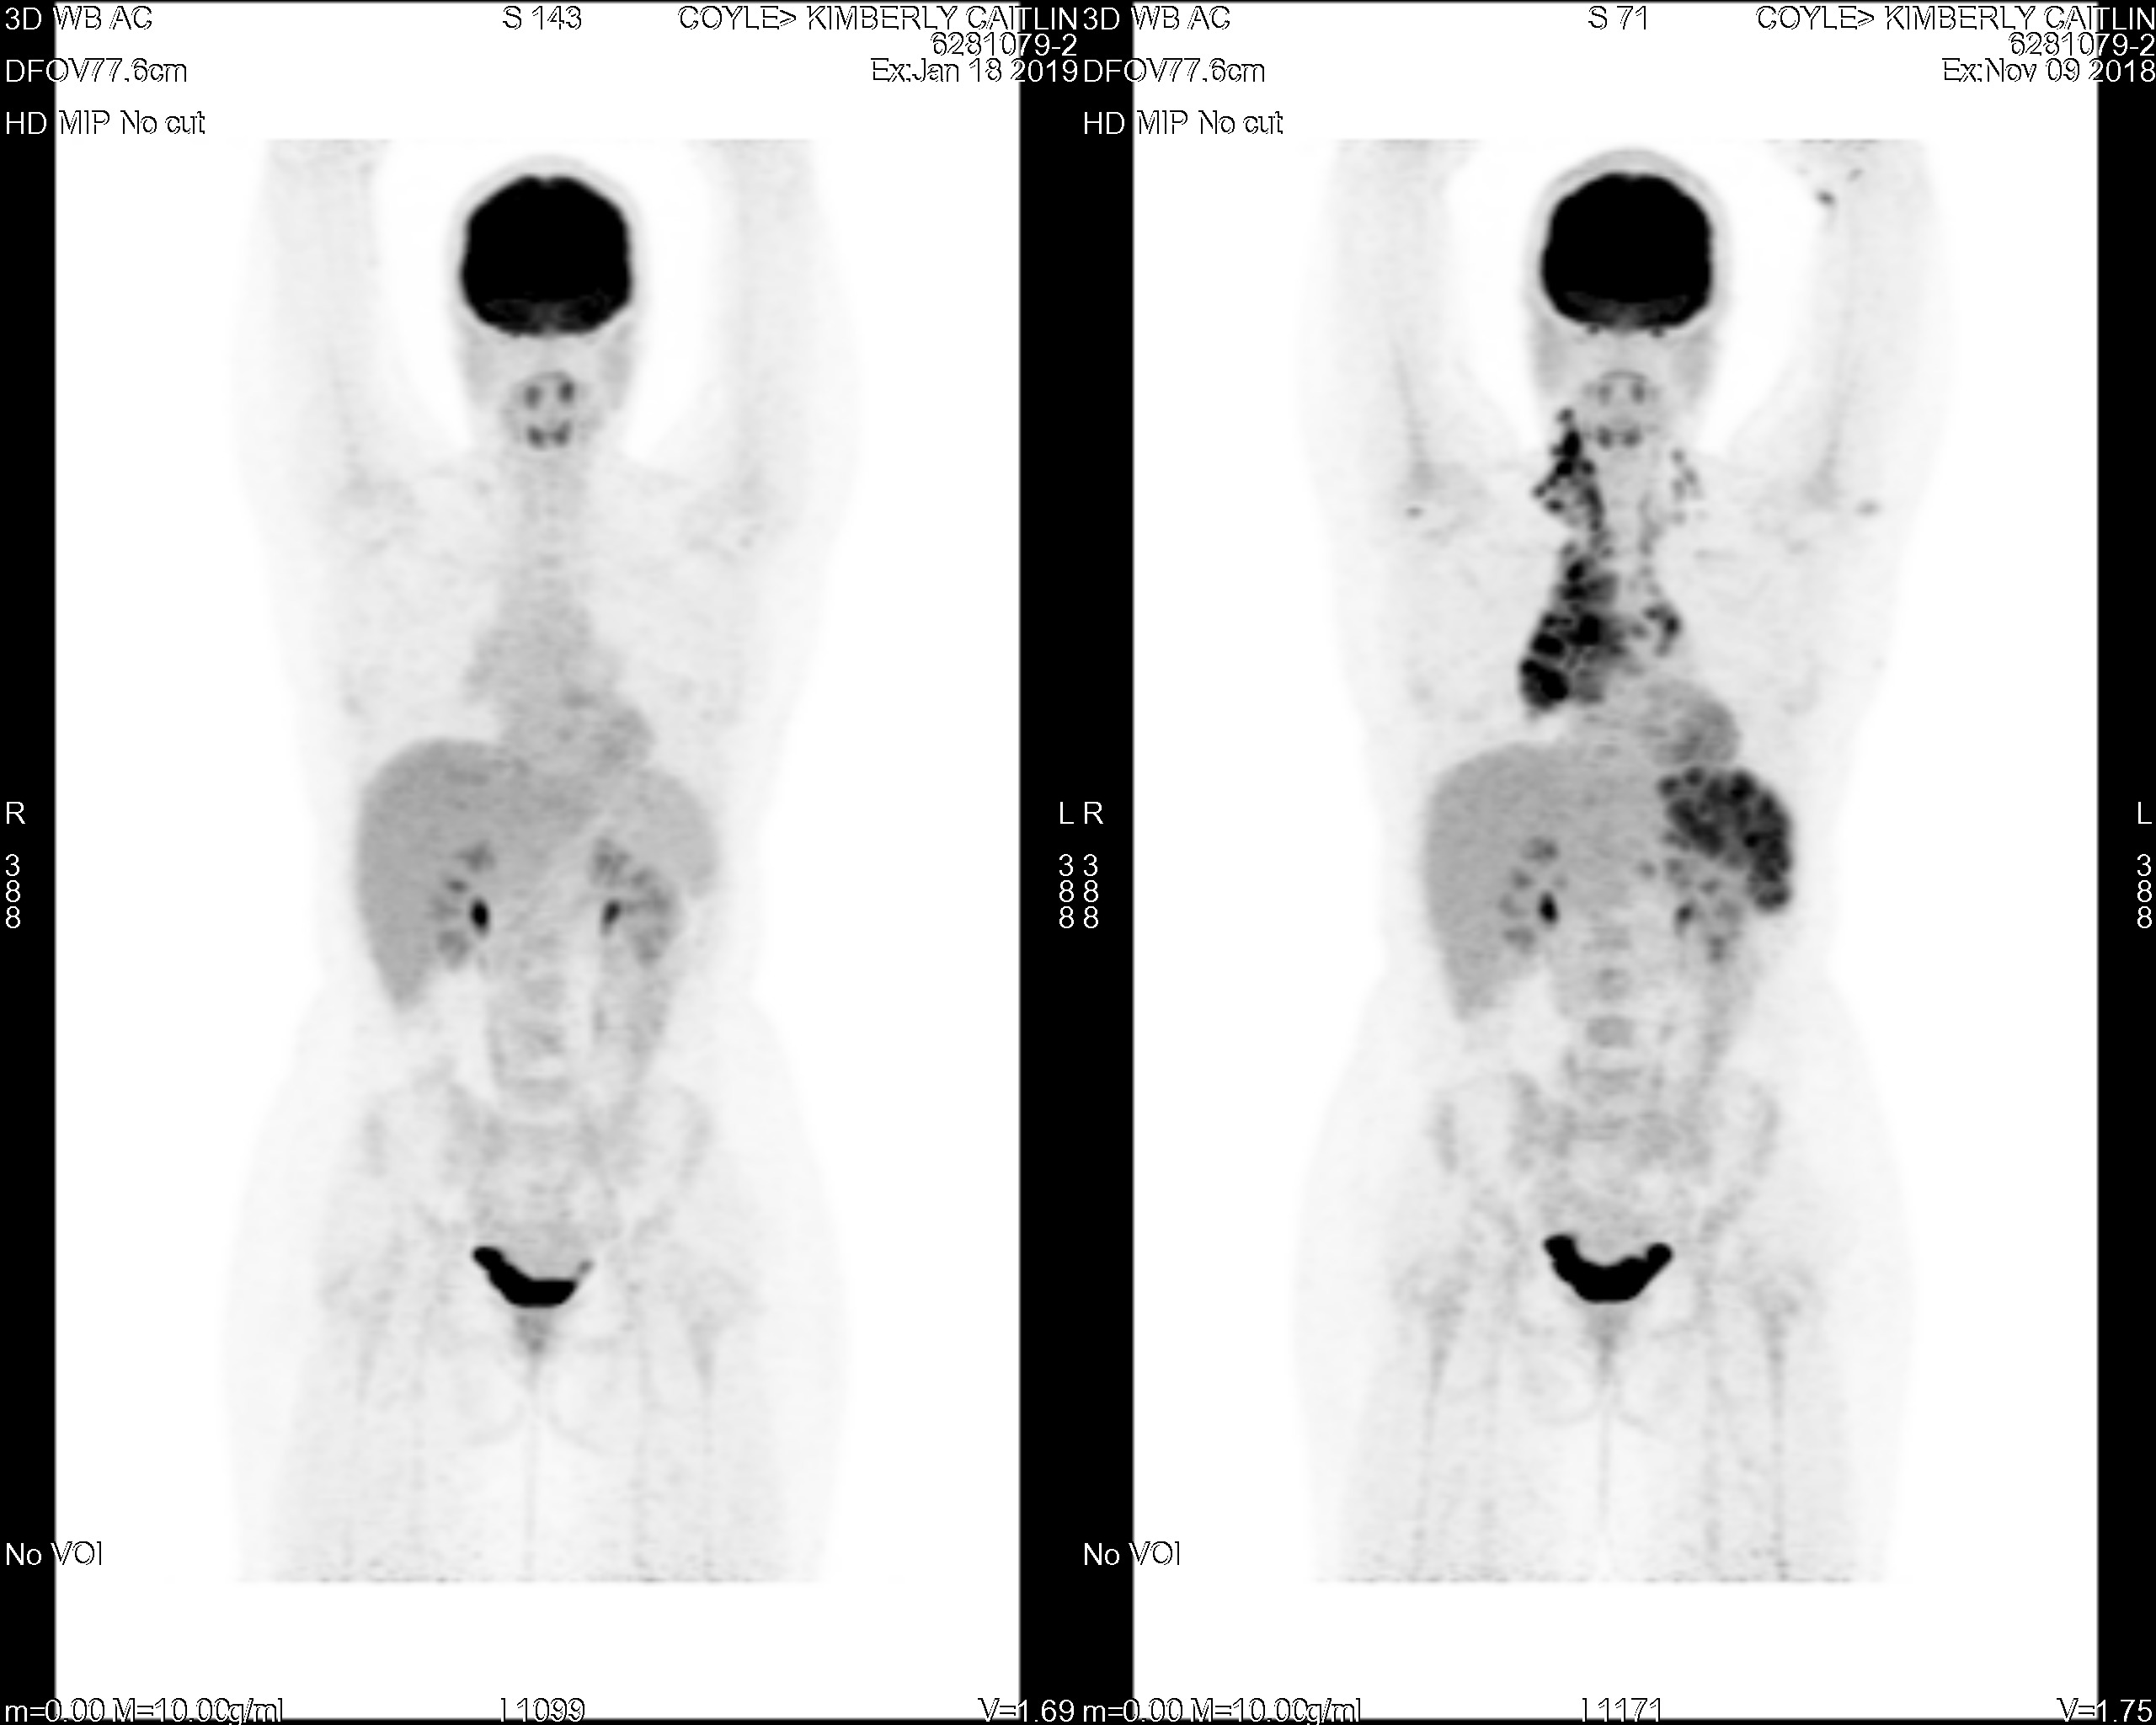

PET Scan Number Two

The Results Are In…Chemo Works

full body scan

January 23, 2019